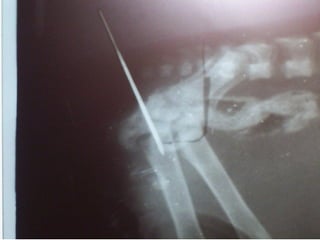

Vía IO

Fémur

Tibia

Ala del íleon